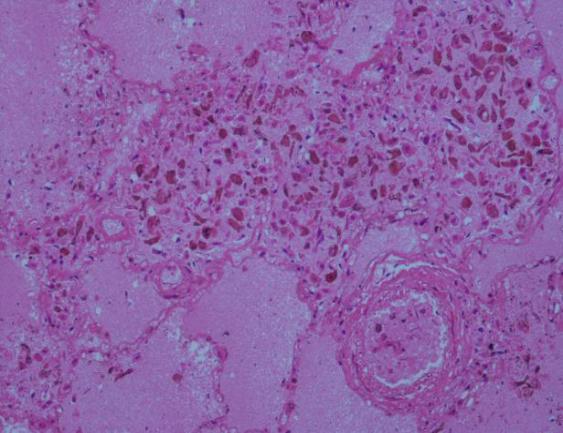

3.病理组织学检查:脑组织毛细血管广泛淤血,未见出血及坏死灶;右冠状动脉狭窄(图9),左心室前壁心肌细胞呈嗜伊红色增强,心肌细胞排列紊乱,心肌纤维增长增粗,部分区域可见大面积新鲜坏死区,心肌轮廓尚存,细胞核消失,核缩、核溶,胞浆呈均质细颗粒状,间质有大量中性粒细胞浸润,坏死心肌组织间有新鲜凝血块,部分区域可见心肌组织被大量的纤维组织代替(图11、图12);肺泡壁毛细血管扩张淤血,肺泡壁增厚,肺泡腔内充满大量粉红色液体并有少量红细胞,部分区域可见到心衰细胞(图10);肝细胞排列整齐,毛细血管扩张淤血,无假小叶形成,汇管区未见异常细胞;脾窦扩张,淤血,脾小体中央动脉无异常改变;胰自溶,结构模糊,胰间质及周围脂肪组织未见灶性坏死;双侧肾脏皮髓质分界清晰,肾小球毛细血管正常,近远曲小管细胞肿胀,间隙增宽,呈淤血改变。

(图9)右冠状动脉狭窄(图10)肺水肿及“心衰细胞”

(图11)心左前壁细胞呈嗜伊红色、心肌细胞坏死(图12)心左前壁细胞呈嗜伊红色、心肌细胞坏死